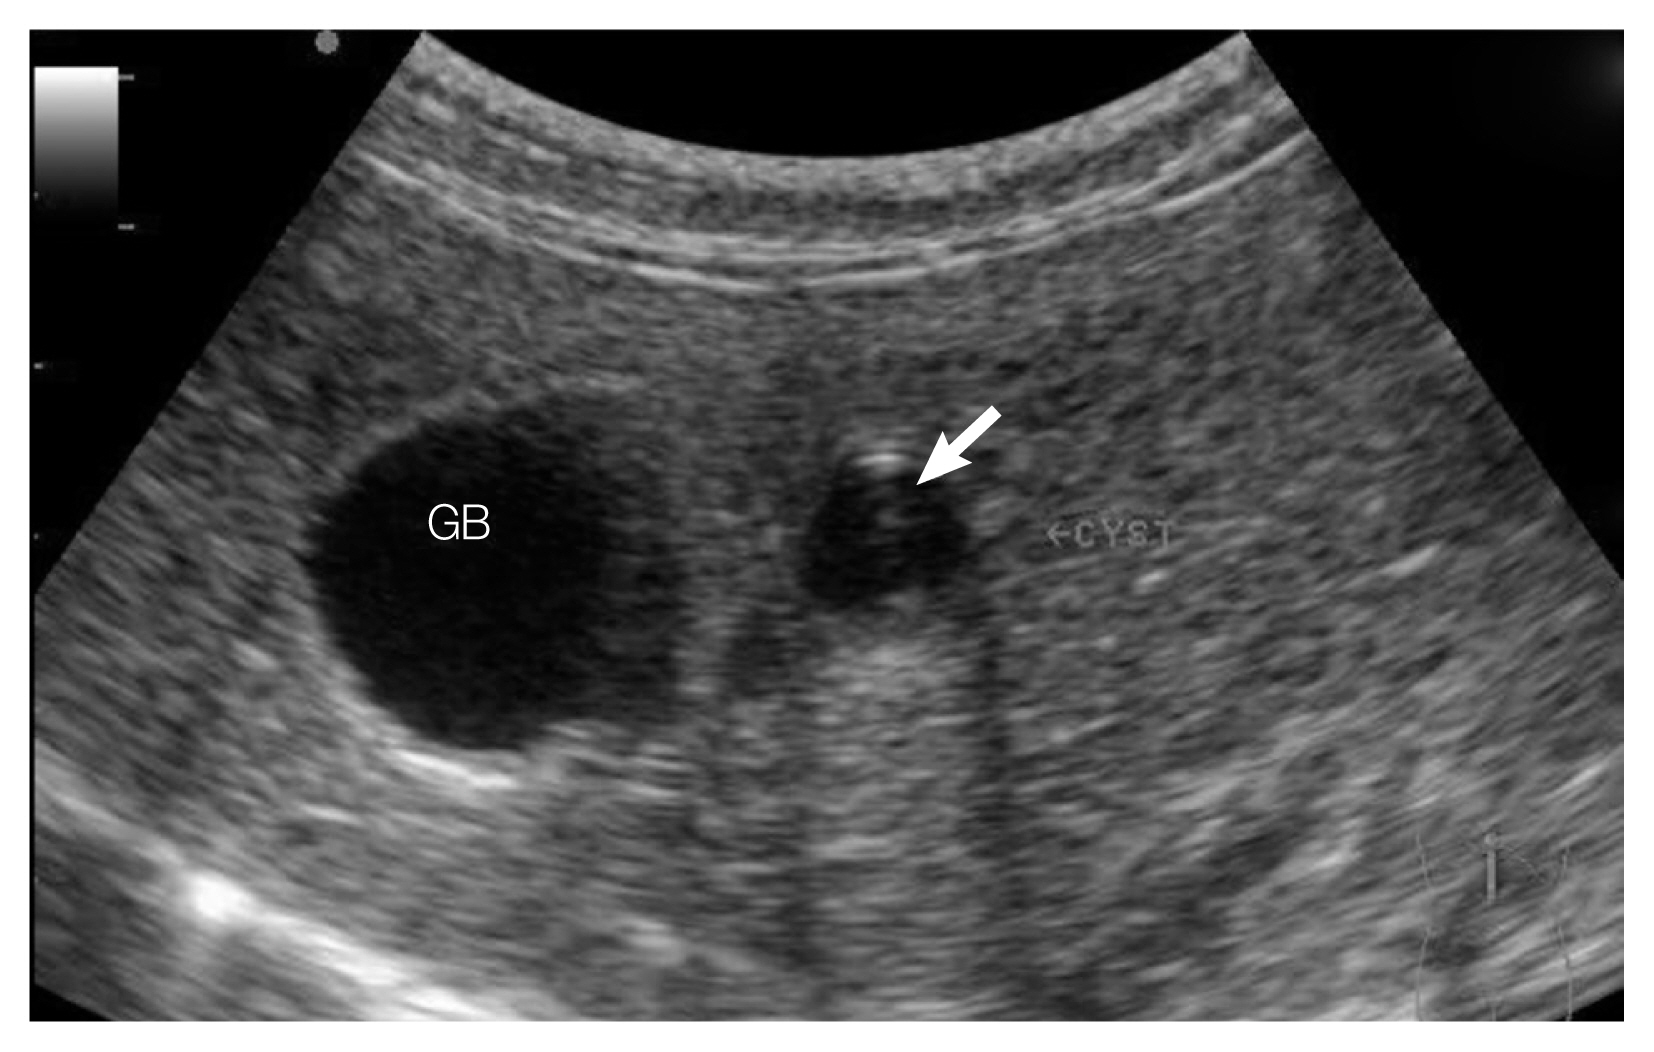

A Clonorchiasis Case of a Leopard Cat, Prionailurus bengalensis euptilurus, Diagnosed by Ultrasonography and Egg Detection in Republic of Korea

The Korean Journal of Parasitology 2019;57(3):299-302.